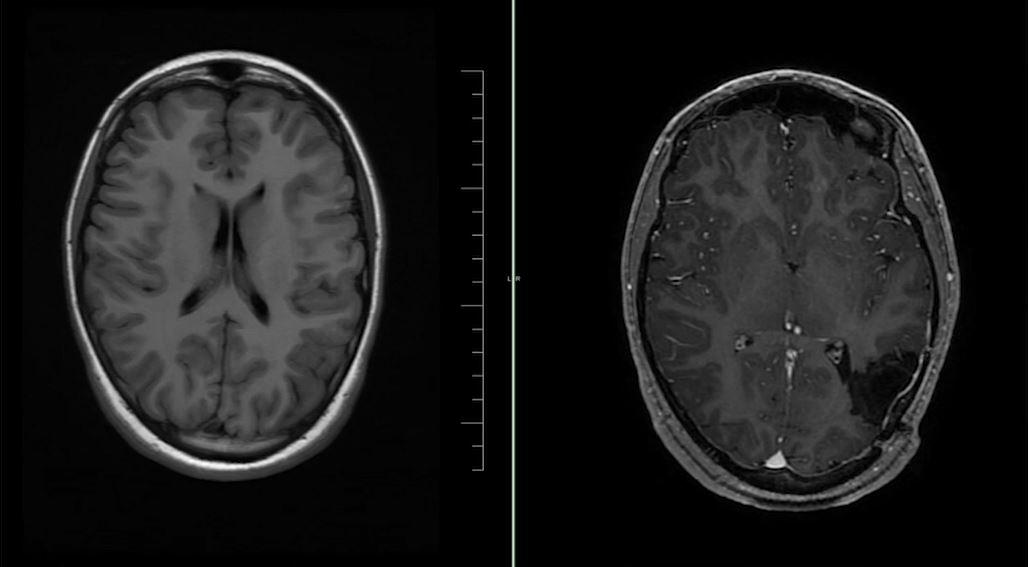

Nová šance na trvalé odstranění záchvatů